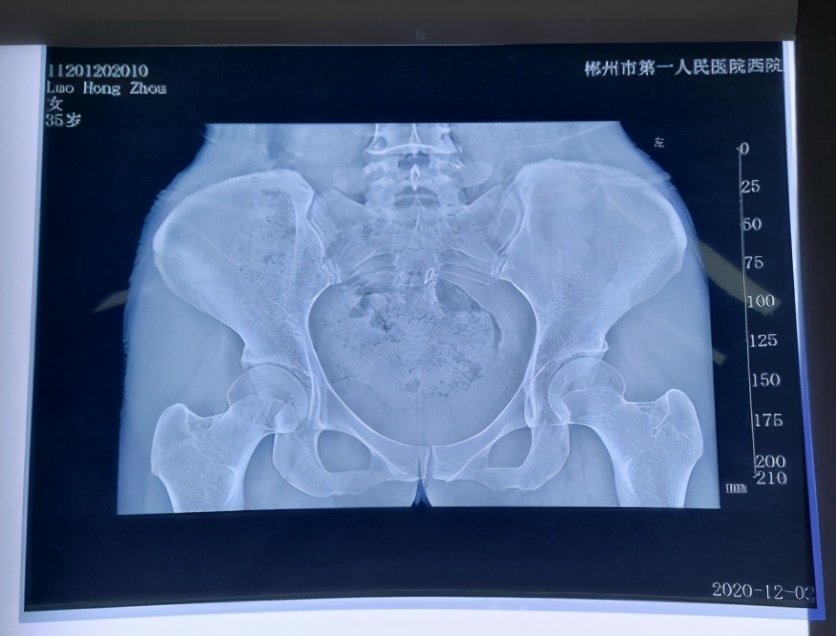

冯主任团队为患者进行了详细的体格检查和评估,检查结果显示舟舟骨盆旋转倾斜,腰腹部核心肌群力量不足。

骨盆右倾旋转